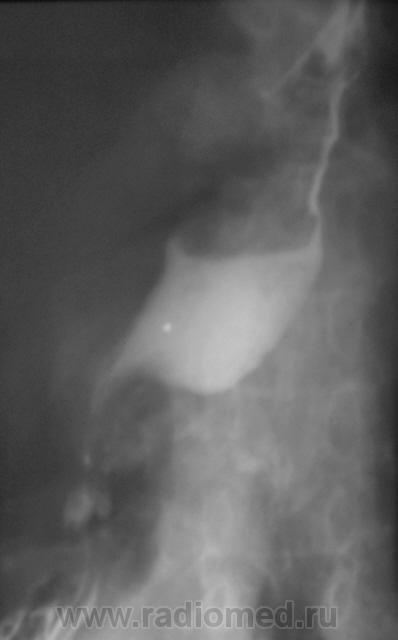

tatyana wrote:

Валентин Львович, а при рентгеноскопии Вы не видели колебания дистального отдела пищевода от передаточной пульсации?

Конечно, видел. Сердце-то огромное. Вот томограммы, которые остались в "заначке".

Томограмма.